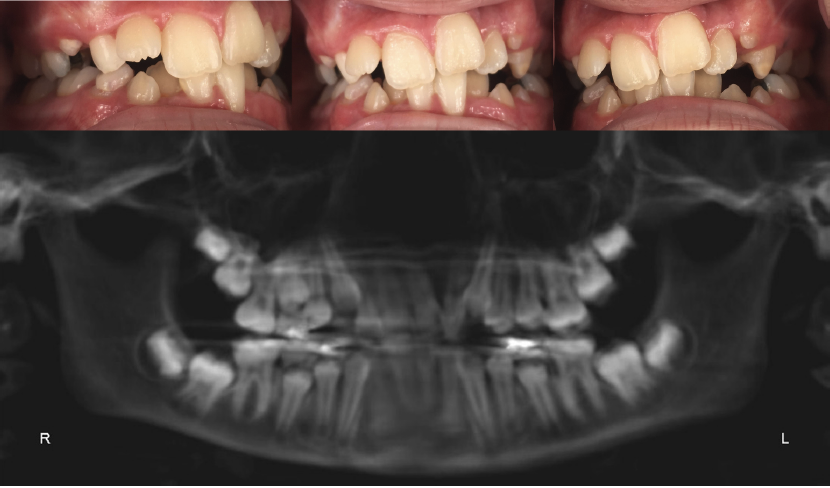

Fig 1. An 11-year-old girl presented with severe crowding and maxillary and mandibular hypoplasia. Previous recommendation was serial extraction of the remaining primary teeth and

the four bicuspids. The patient presented to the author’s practice office seeking alternative treatment for phase 1 utilizing expansion.

Fig 4. Pretreatment (left panel) and peri-treatment (right panel) smile, frontal view.

Figure 4

Fig 5. Right lateral view, frontal view, and left lateral view pretreatment (top panels) and peri-treatment (bottom panels).

Figure 5